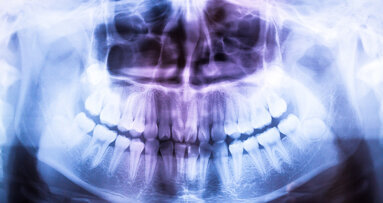

UTRECHT – Vanaf volgende maand gelden er nieuwe regels op het gebied van radiologie. Zo gaat voor tandartsen die röntgenopnamen maken een nascholingsplicht gelden. Die plicht geldt eveneens voor personeel dat opnamen maakt in opdracht van de tandarts. Dat meldt beroepsvereniging KNMT.

Met ingang van 6 februari 2018 treedt het Besluit Basisveiligheidsnormen stralingsbescherming (Bbs) in werking. De nascholingsplicht houdt in dat tandartsen eens per vijf jaar moeten aantonen dat zij voldoende nascholing op het gebied van radiologie hebben gevolgd.

Een andere belangrijke verandering uit de nieuwe regelgeving is dat voor Conebeam CT een volledige vergunningsplicht gaat gelden, ook voor output lager dan 100 kV. Daarnaast vervalt de meldplicht van röntgenapparatuur en gaat in plaats daarvan een registratieplicht gelden. Dat geldt voor alle röntgentoestellen. Verder moet onder de nieuwe regelgeving de naam van de stralingsdeskundige (voorheen coördinerend deskundige) worden vermeld in het KEW-dossier.